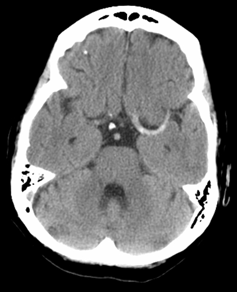

In the hyperacute setting of a stroke what may a brain CT scan show?

May be essentially normal :( but may show hyperdense middle cerebral artery for example